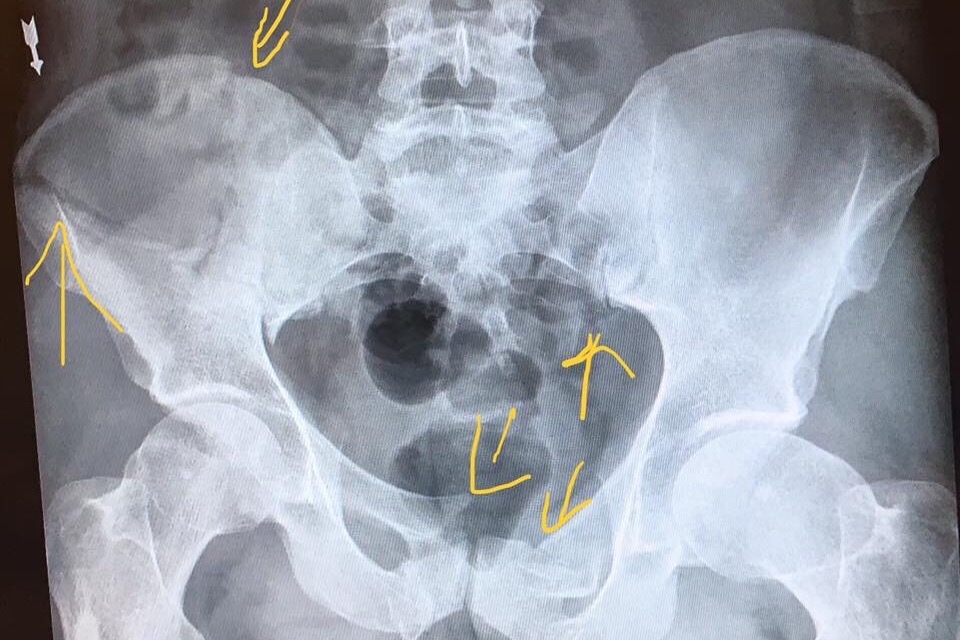

Our son, friend, co-worker, etc., Matt Thurmond, was on his way to work on his bicycle. He left his house at 3:30am on Sunday 9/16/18. Approximately 10 minutes later, he was hit by a vehicle and the driver left him laying unconscious on the side of the road. He laid there for approximately 20-25 minutes, waking up at some point, in the dark, unable to get up. He tried to flag down a couple of cars that passed by but they didn’t see him. Finally, a deputy who happened to take a wrong turn saw him and he was taken by flight for life to UMC trauma. He suffered broken facial bones around his eye and cheek, bruised lungs, broken ribs, a lacerated liver, a badly cut knee, and a broken pelvis, along with road rash all over. But he survived!! He won’t be able to work for some time and is of course amassing medical bills that he’ll have to deal with if the driver isn’t found. So he needs all the help he can get, not just for the medical, but his regular monthly bills. Those that know Matt, know he helps whomever he can. Now he needs a hand. Even if it’s just sharing this so it gets more attention, it’s greatly appreciated. Thank you in advance